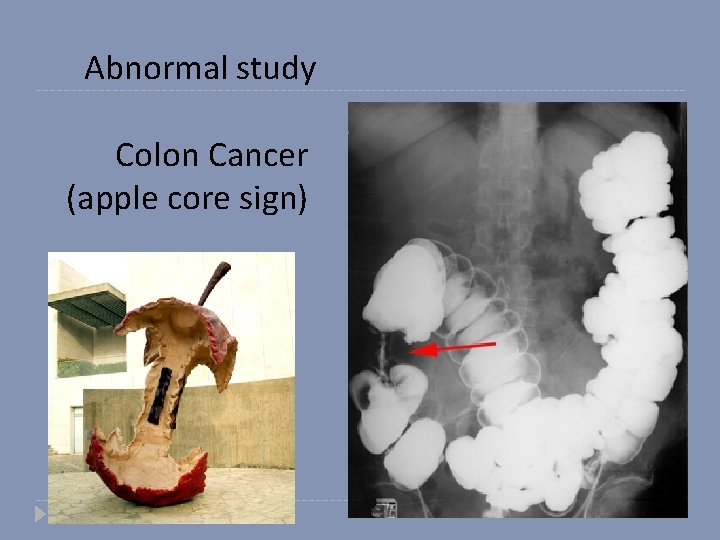

Is this study normal or abnormal? And why?

Abnormal study Colon Cancer (apple core sign)

Apple core sign